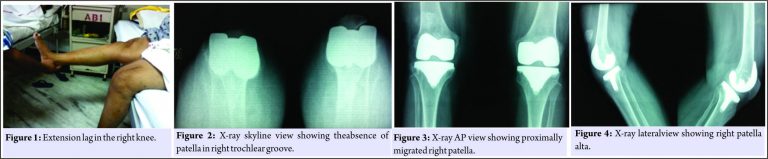

A 69-year-old woman underwent bilateral total knee replacement for symptomatic Grade III osteoarthritis of both the knees. The surgery was performed using a midline skin incision and midvastus approach. A cemented cruciate substituting posterior stabilized implant(Stryker NRG Scorpio, right knee femoral component size 4, tibial component size 4,and insert thickness 8 mm and left knee femoral component of size 5, tibial component size 4, and insert thickness 10 mm) was used. The patella was everted during surgery as usual and patelloplasty was done. She recovered well in the post-operative period,attaining range of motion from 0 to 90° by the end of 1st week of surgery, and could walk comfortably without support 4 weeks after the surgery.She did not report until about 6 months after surgery when she started having difficulty in walking with right knee and in getting up from sitting position.She did not have any pain and did not report any trauma. On examination, she had an extension lag of 30° and could flex up to 110° (Fig. 1).

The knee was not warm orerythematous, but patella was located higher than normal. There was minimal tenderness around patellar tendon and tibial tuberosity, and x-ray revealed patella alta on the right side which led to the diagnosis of patellar tendon avulsion (Fig. 2, 3, 4). On exploration, patellar tendon was found to be avulsed from tibial tuberosity with 8–10 cm proximal migration of patella and extensive fibrosis in between (Fig. 1). After debridement, the patella was mobilized down to its normal position only with aquadriceps snip.The semitendinosus tendon was harvested through a small incision over the pes anserinus using tendon stripper, keeping its tibial attachment intact. One 6 mm wide tunnel was drilled horizontally into the tibial tuberosity and one transversely in the upper half of the patella. The free end of the harvested tendon was first made to pass through the tibial tunnel from medial to lateral direction and was then weaved through the patellar tendon remnant and fibrous tissue in a proximal direction toward patella. It was then made to pass through the patellar tunnel from lateral to medial end and was again weaved through the available scar tissue and carried distally to end just medial to the tibial tuberosity where it was stapled after tensioning at 30° of knee flexion (Fig. 5, 6, 7, 8).